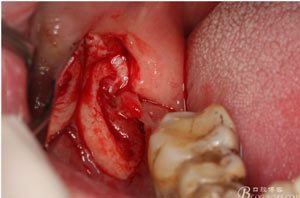

圖6.行角形瓣切開(kāi)、翻瓣、暴露骨面,可見(jiàn)48牙冠表面有炎性肉芽組織